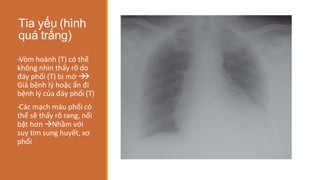

Tia yếu (hình

quá trắng)

-

‐Vòm hoành (T) có thể

không nhìn thấy rõ do

đáy phổi (T) bị mờ 



Giả bệnh lý hoặc ẩn đi

bệnh lý của đáy phổi (T)

‐Các mạch máu phổi có

thể sẽ thấy rõ rang, nổi

bật hơn Nhầm với

suy tim sung huyết, xơ

phổi